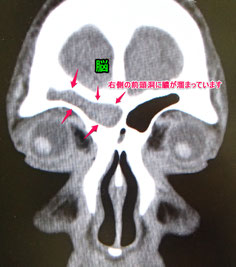

この患者さんも目の内側の重い感じ、痛みにて受診された方です。

篩骨洞という目の内側の副鼻腔に嚢腫という袋ができています。

蓄膿症(副鼻腔炎)の手術を以前に受けた方にまれに見られますが、全く手術を受けたことがない方の例もあります。場合によっては眼を圧迫し、ものが二重に見えたりすることもあります。

こういう嚢腫は、手術で鼻腔側から交通をつけます。